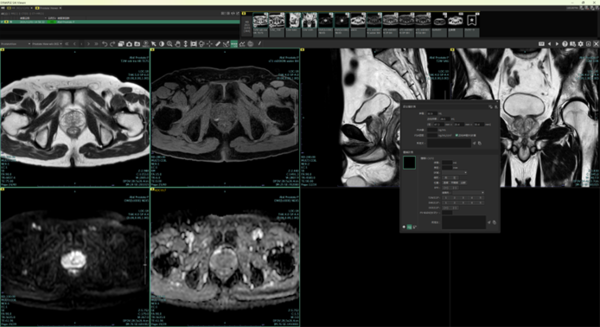

(1) 前立腺ビュー(MR)*4

今回新たに搭載する「前立腺ビュー(MR)」は,最新版であるPI-RADS V2.1に準拠した読影を支援する機能。本機能は,起動と同時にPI-RADS読影専用のダイアログが立ち上がり,自動で前立腺の体積を表示する。医師が血液検査で得られたPSA値を入力すると,自動でPSA密度を算出する。また腫瘍計測をすると,自動で腫瘍のサイズ/区域/側性などを表示する。さらに,医師がT2WI*6/DWI/DCE*7(ダイナミック造影像)の各スコアを入力すると,PI-RADSカテゴリーを自動で算出する。これらの計測情報やカテゴリー情報を用いて,所見文の候補を複数表示することもでき,PI-RADS読影のワークフローを支援する。

前立腺ビュー(MR)のレイアウトイメージ図

前立腺ビューでの読影支援機能。 腫瘍計測をすると,自動で腫瘍のサイズ/区域/側性などを表示する。 また,医師が選択した各画像スコアに基づき,PI-RADSカテゴリーを自動算出する。